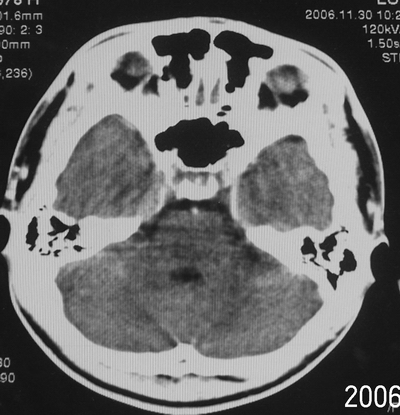

患者、男、18y,头痛5天入院。

左小脑、右丘脑区低密度影,无明显强化及占位表现,男18y,先考虑脑部炎性病变,如脑炎、血行播散性感染等,建议结合临床如脑脊液检验。

单独看左侧小脑半球的不规则形囊性低密度灶,从发病部位、年龄以及无强化、无占位效应的特点可以考虑毛细胞瘤型星形细胞瘤。同样,如果单独看右侧丘脑的近圆形低密度,也可以考虑囊变形星形细胞瘤。只是胶质细胞瘤一般为单发直接浸润、蔓延生长,而不是在脑内同时出现多个病灶,且瘤周没有一点儿水肿,暂时不予以考虑。

脑炎倒是首先可以考虑,只是临床症状、病史不很符合,建议狼兄仔细了解病史以及其他临床资料。

同时,现在已经进入冬天,一氧化碳中毒也需要考虑进去。不知道增强是什么时间做的,与平扫间隔几天?如果中间时间比较久而且进行吸氧等治疗,则平扫所示右侧颞叶密度比较低、右侧小脑半球以及脑桥也似有片囊状低密度,但在增强却没有发现就可以比较合理的解释了。